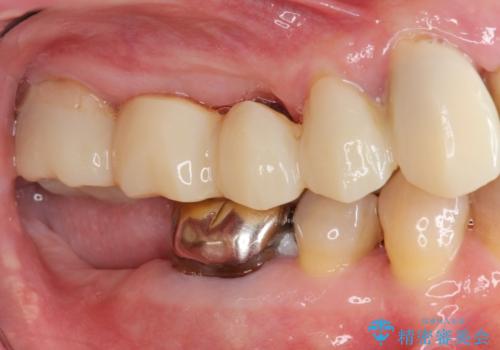

- 他院で上顎は全て抜歯し、入れ歯にする必要があると言われ相談に来院されました。

検査の結果、重度の歯周病であることから保存が難しい歯は抜歯を行いインプラントを、残すことが可能な歯には再生治療を含めた歯周病治療を行いより多くの歯を残す歯周病治療を計画します。

上顎は、残っている前歯も揺れがあり残すためにはクラウンでつなぐ歯周補綴が必要な状態です。

また咬合負担に不安のある前歯を助けるためにも、臼歯部にインプラント補綴を行いしっかりとかめる状態とすることも大切です。